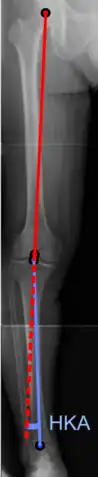

Hip-knee-ankle angle.

There are two disorders relating to an abnormal angle in the coronal plane at the level of the knee:

• Genu valgum is a valgus deformity in which the tibia is turned outward in relation to the femur, resulting in a knock-kneed appearance.

• Genu varum is a varus deformity in which the tibia is turned inward in relation to the femur, resulting in a bowlegged deformity.

The degree of varus or valgus deformity can be quantified by the hip-knee-ankle angle,[33] which is an angle between the femoral mechanical axis and the center of the ankle joint.[34] It is normally between 1.0° and 1.5° of varus in adults.[35] Normal ranges are different in children.[36]